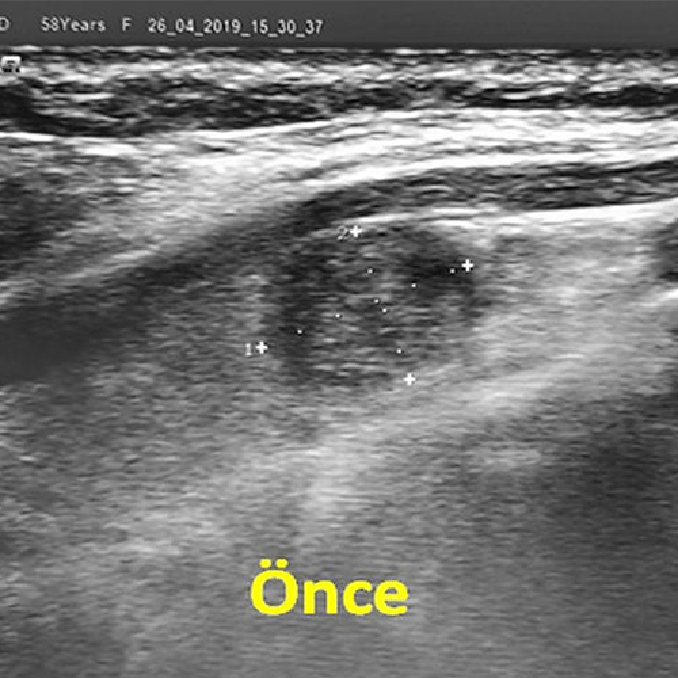

Önce, ultrason ile tiroiddeki ablasyon yapılacak nodül tesbit edilir. Daha sonra, ciltte giriş yeri lokal anestezi ile uyuşturulur ve uygun boyutlu kriyoablasyon iğnesi ultrason rehberliğinde nodüle yerleştirilir. Bu aşamada, cihaz çalıştırılarak dondurma işlemine başlanır. Kriyoablasyon sırasında, nodülün merkezindeki iğnenin çevresinde hızla bir buz topu oluşur. Siyah bir alan olarak görülen buztopu gittikçe büyüyerek tiroid nodülünü tamamen içine alır ve dondurarak öldürür. Nodülün tamamen ölmesi için genellikle dondurma işlemi 2-3 kez tekrarlanır. İşlem sırasında, nodül çevresine sıvı verilerek çevredeki sinirler korunur. Ayrıca, hasta aralıklı olarak konuşturularak ses teli sinirinin fonksiyonu kontrol edilir. İşlem bittikten sonra kriyoablasyon iğnesi çekilir ve hasta birkaç saat gözlendikten sonra taburcu edilir.

Sol tiroid lobunda rastlantısal olarak saptanan 13 mm çaplı papiller karsinomu olan 50 yaşında bir kadın hastada perkütan kriyoablasyon tedavisi uygulanmıştır. İşlem sırasında ultrasonda, tümörü tamamen kaplayan büyük bir buz topu izlenmiştir. On ay sonra, ultrasonda nodül izlenememiştir.

Kriyoablasyon, bu açılardan tiroiddeki kanser şüphesi taşıyan ya da kanser tanısı alan nodüller için daha uygun bir ablasyon yöntemidir. Bu yöntemde iğne nodülün ortasına yerleştirilir ve ablasyon bitene kadar hareket ettirilmez. Ayrıca, oluşan buz topunun nodülü tamamen kapladığı ultrasonda görülebilir ve tümörün tamamen öldürüldüğünden emin olunabilir. Buz topu cilt, damar ve sinirlere yaklaşırsa bu da hemen görülebilir ve bu yapıları korumak için gerekli tedbirler alınabilir.

Sol tiroid lobunda 11 mm çaplı papiller karsinomu olan 59 yaşındaki kadın hastamıza perkütan kriyoablasyon uygulandı. Dokuz ay sonra, nodül ultrasonda görülememiş ve 1.5 yıllık takip boyunca hastada herhangi bir nüks olmamıştır.